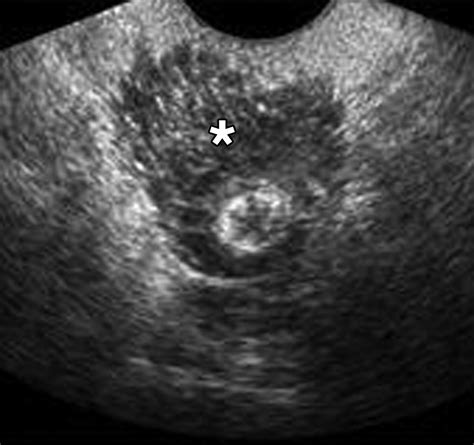

Diagnosing conditions affecting the Posterior Cul De Sac often involves a combination of medical history, physical examination, and diagnostic tests. Some of the most common diagnostic techniques include:

• MRI: An MRI uses magnetic fields and radio waves to create detailed images of the body's internal structures. This test can provide valuable information about the Posterior Cul De Sac and surrounding tissues.